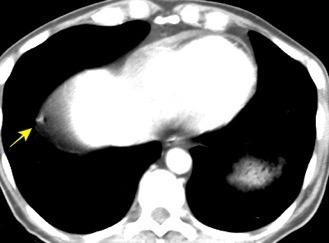

Carcinoma de mama con derrame pleural e implantes metastáticos

Makis W et al. Spectrum of Malignant Pleural and Pericardial Disease on FDG PET/CT. AJR. 2012